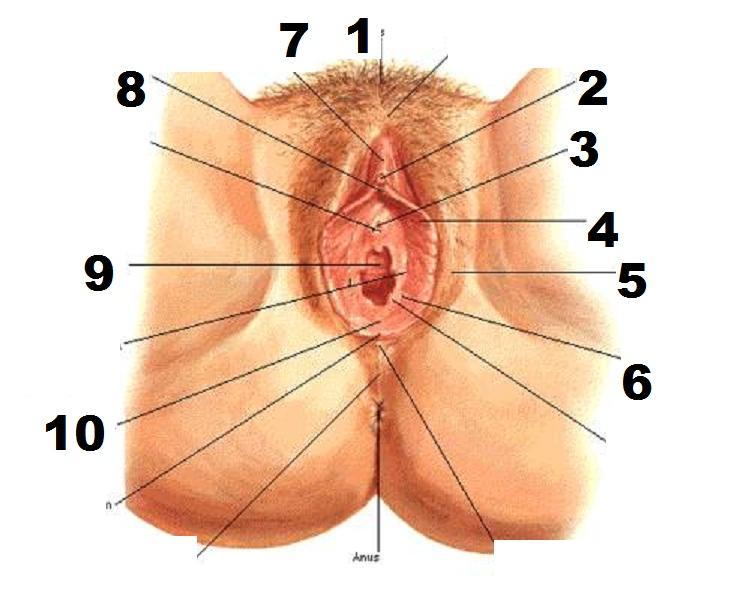

Clitoris

External urethral orifice (female)

Labia majora/minora

Prepuce (=clitoral hood)

Vaginal orifice

Vestibule (of vulva)